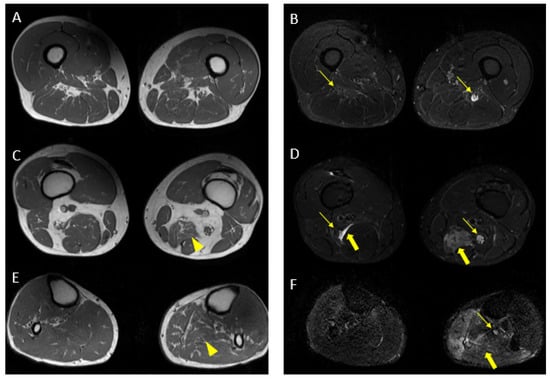

Figure 9.

Pathological alterations of the left sciatic nerve (thin arrows in (B,D)), characterized by a significant increase in volume (CSA in the upper third of the thigh of about 123 mm2) with associated fascicular hypertrophy and an increase in signals in T2w images, especially in the height of the middle and lower third of the thigh and with extension to the tibial nerve (thin arrow in (F)), up to the lower third of the leg. Also, in the right sciatic nerve, there are some alterations (thin arrows in (B,D), much more tenuous than the contralateral nerve, characterized by an increase in the thickness of the nerve (CSA at the upper third of the thigh of about 110 mm2), a moderate increase signal in T2w images and fascicular hypertrophy, without evident tibial nerve signal alterations. Mixed denervation, acute and chronic, of left and right semimembranosus and posteromedial compartment muscles of the left leg (muscle hyperintensity and fascial edema in STIR, thick arrows in (D,F)) and fat replacement (muscle bundle atrophy with replacement of hyperintense tissue at T1W in (A,C,E), more evident in some areas: arrowheads in (C,E)).